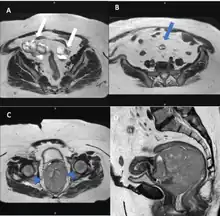

Computed tomography

Computed tomography (CT) scans is a diagnostic x-ray procedure that generates detailed cross-sectional images of the body, facilitating the detection of potential ovarian cancer spread to other organs.[16] While CT scans may not effectively visualize small ovarian tumors, they have the capability to detect larger tumors and evaluate their potential invasion into nearby structures. Additionally, CT scans can identify enlarged lymph nodes, signs of cancer spreading to the liver or other organs, and indications of an ovarian tumor impacting the kidneys or bladder. Although CT scans are not commonly used for biopsying ovarian tumors, they can be utilized in the biopsy of suspected metastases through a technique known as CT-guided needle biopsy.[16]

The difficulty in screening for SCC revolves around the creation of effective strategies with a positive predictive value. The timing aspect is crucial due to the lack of a specific timeframe for the onset of invasive disease or the interval stage between stage I and stage III carcinomas.[17] Ultrasound screening provides a detailed view of the ovaries, identifying morphologic changes as potential signs of malignancy. Key diagnostic factors include the presence of abnormalities, ovarian size, blood flow, and abdominal/pelvic fluid. The persistence of abnormalities after four to six weeks may decrease the occurrence of false positives. Screening protocols, often based on morphologic indices, utilize transvaginal ultrasound findings like cyst wall structure, septation, papillary projections, echogenicity, and ovarian volume to effectively detect malignancy.[17]

Magnetic resonance imaging

Although magnetic resonance (MRI) scans are not commonly employed for ovarian cancer detection, the majority of ultrasound-detected ovarian masses are usually benign. The combined approach of ultrasound with Doppler, along with the selective use of contrast-enhanced MRI, proves to be an efficient diagnostic method for identifying benign adnexal masses with distinctive features, including functional masses, dermoid, endometrioma, fibroma, pedunculated fibroid, hydrosalpinx, and peritoneal inclusion cysts.[19] This integrated diagnostic strategy is effective in preventing unnecessary surgical intervention. Additionally, the use of MRI contributes to a decrease in false-positive diagnoses, ultimately reducing the overall number of unnecessary surgical procedures related to ovarian masses.